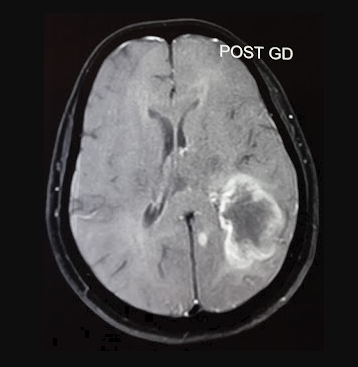

Çalışmanın Odak Noktası: Calgary Üniversitesi araştırmacıları, en agresif beyin kanseri türü olan glioblastomaya karşı, standart tedaviye (ameliyat, radyasyon, kemoterapi) ek olarak yüksek doz B3 vitamini (niasin) kullanımını araştırmaktadır.

Erken Dönem Sonuçları: 24 hasta ile yürütülen klinik denemelerin ilk aşaması oldukça olumludur. Hastaların %82'sinde 6 ay sonrasında hastalığın ilerlemediği görülmüştür. Bu oran, önceki standart tedavi verilerine kıyasla %28'lik dikkate değer bir iyileşme anlamına gelmektedir.